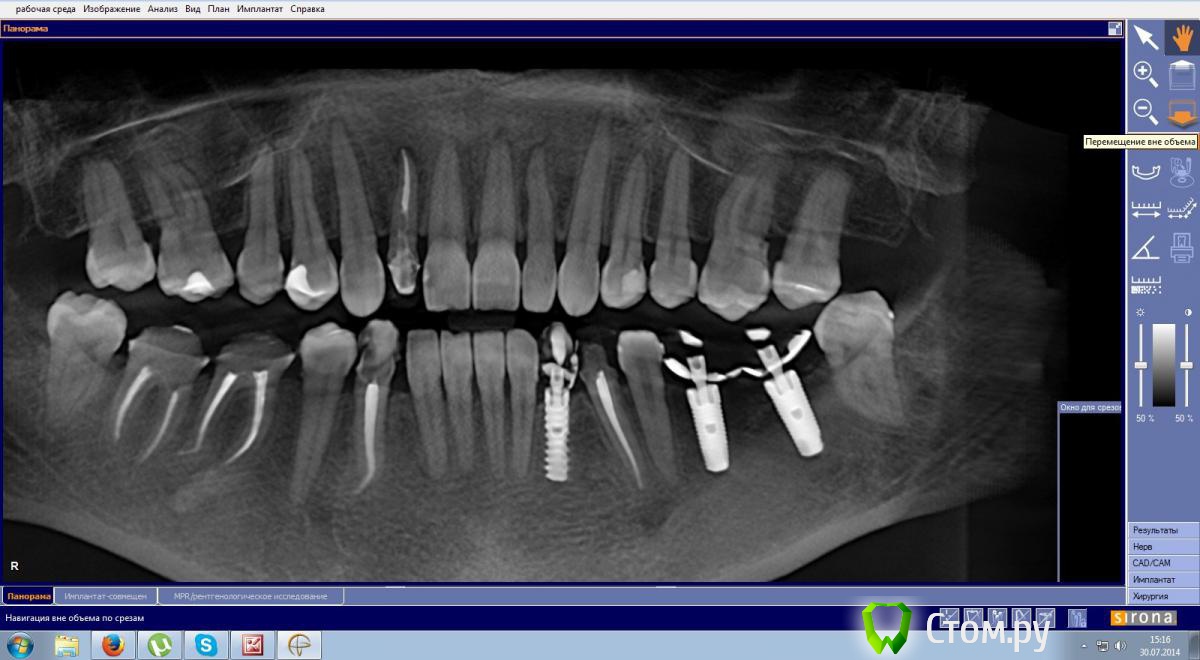

Эндж Опубликовано 30 июля, 2014 Поделиться Опубликовано 30 июля, 2014 Здравствуйте! Прокомментируйте, пожалуйста состояние моих зубов. Сейчас после ортодонтии и имплантации ношу пока времянки, через неделю планируется установка постоянных. Я вижу на двойке сверху гранулемуи мне кажется, что она увеличилась. Мой ортопед говорит, что канал хорошо пролечен и лучше не трогать, а я переживаю, что после установки постоянной коронки может начаться какая-нибудь проблема.Канал перелечили два с половиной года назад. Снимки:1) до перелечивания2) год назад3) и 4) вчера Ссылка на комментарий

red_butler Опубликовано 5 августа, 2014 Поделиться Опубликовано 5 августа, 2014 Коффедарма точно не было, а про запах хлорки не помню. А по снимку не видно качественно пролечен или нет?по снимку нормально пролечен. Соглашусь с M@estro -делать резекцию апекса Ссылка на комментарий

Эндж Опубликовано 9 августа, 2014 Автор Поделиться Опубликовано 9 августа, 2014 по снимку нормально пролечен. Соглашусь с M@estro -делать резекцию апексаСкажите, пожалуйста, а вы видите в канале этого зуба СВШ? Доктор видит, а мне вроде его не ставили. И вопросик по остальным зубам с пролеченными каналами. Ортопед сказал, что во все каналы нужно поставить стекловолокно. Своих тканей на зубах вроде достаточно, премоляры депульпировали полностью здоровые, без пломб, только двойка сильна обточена. Ссылка на комментарий

red_butler Опубликовано 9 августа, 2014 Поделиться Опубликовано 9 августа, 2014 Скажите, пожалуйста, а вы видите в канале этого зуба СВШ? Доктор видит, а мне вроде его не ставили. И вопросик по остальным зубам с пролеченными каналами. Ортопед сказал, что во все каналы нужно поставить стекловолокно. Своих тканей на зубах вроде достаточно, премоляры депульпировали полностью здоровые, без пломб, только двойка сильна обточена.вкладки нет, похоже стоит стекловолокно. Эндодонтическое лечение зубов хорошее. Если судить только по снимку, я бы рекомендовал делать вкладки и коронки. Но единого мнения по этому вопросу нет. Нужен очный осмотр. 2 Ссылка на комментарий